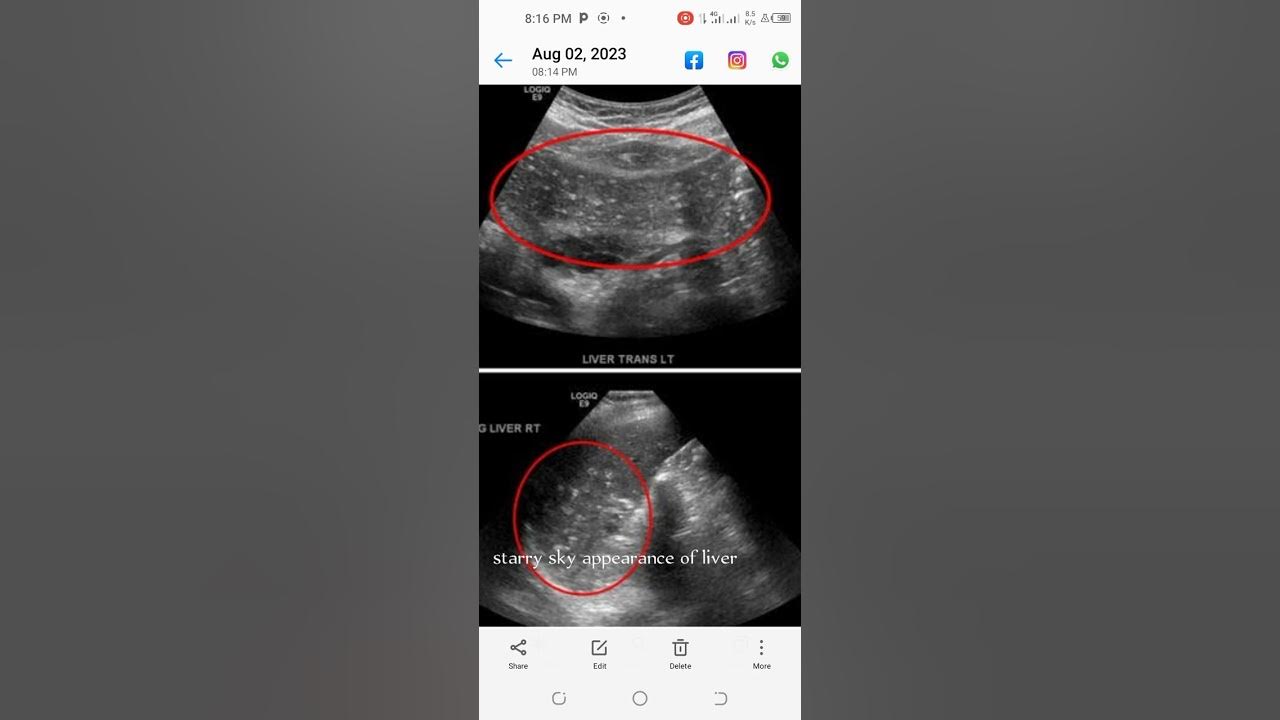

ultrasound-signs-starry-sky-appearance-of-liver-youtube

Ultrasound Signs starry Sky Appearance Of Liver YouTube

acute-viral-hepatitis-or-liver-inflammation-ultrasound-and-color

Acute Viral Hepatitis Or Liver Inflammation Ultrasound And Color